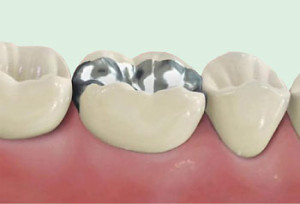

ПЛОМБЫ

Пломбы из амальгамы (серые, серебрянные пломбы) являются простым и быстрым решением, но по эстетическим причинам все меньше используются в современной стоматологии.

Композитные пломбы (белые пломбы) намного более выгодны с точки зрения эстетики. Химическая связь, возникающая между зубом и такой пломбой, препятствует проникновению бактерий и не ослабевает в процессе жевания. Современные композиты обладают так называемым эффектом хамелеона – приобретают цвет зубной ткани с которой вступают в контакт и, при этом, сохраняют отличные механические и биологические свойства.